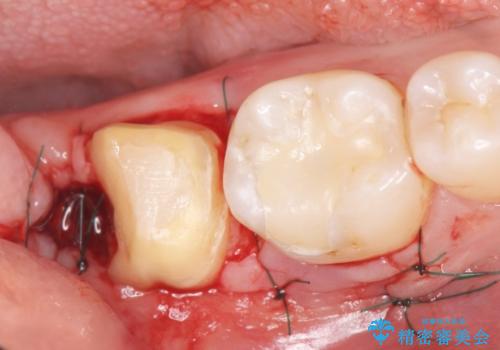

精査したところ、右下の一番奥の歯(右下7)に歯肉縁下に及ぶ深いう蝕を認めました。

神経がない歯であり痛みが出ないことから、自覚症状がほとんどなくう蝕が大きく進行してしまったと考えられます。

銀歯を除去し、歯周外科処置(右下7遠心の骨整形及びディスタルウェッジ)を行った後にメタルボンドクラウンによる補綴を行いました。

歯周外科処置(右下7遠心の骨整形及びディスタルウェッジ)により、深部に及ぶう蝕を除去するとともに歯肉縁上の健全歯質を獲得でき、適合の良い被せ物を作製することができました。